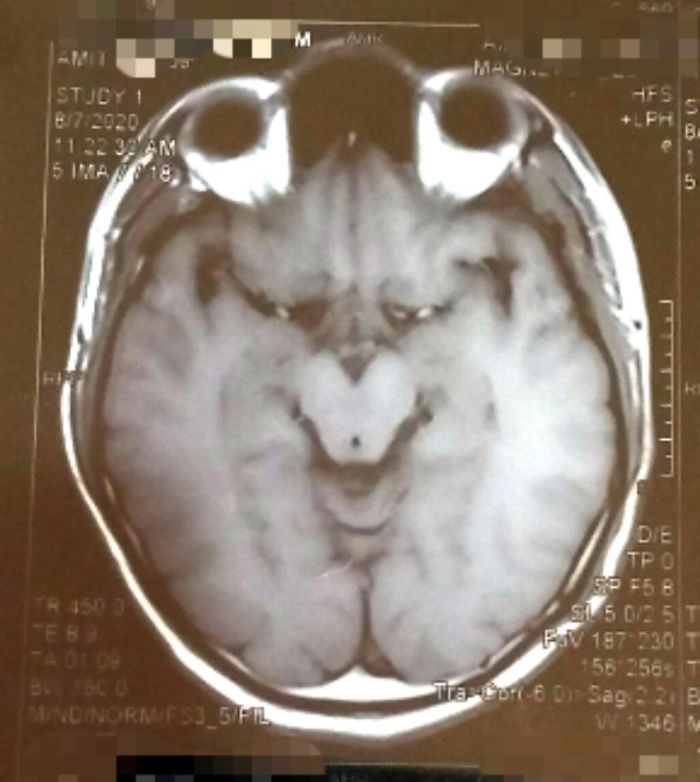

La resonancia de mi cerebro se parece al Grinch